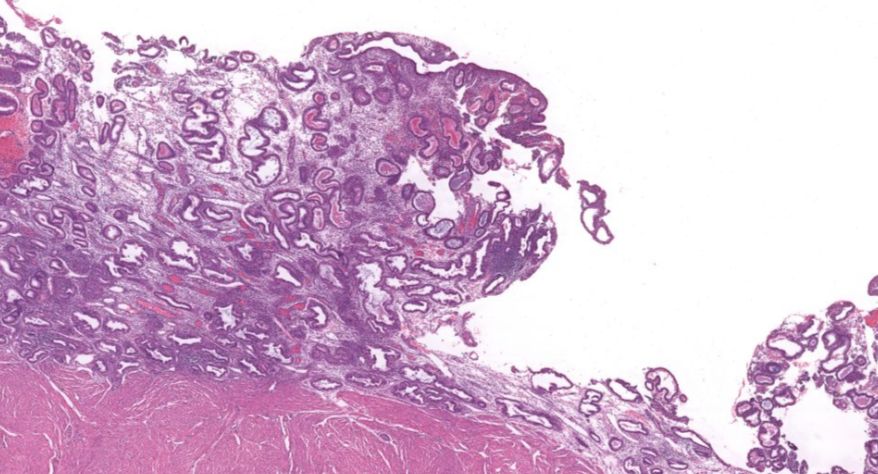

3 子宫内膜异位症

3.子宫腺细胞增生